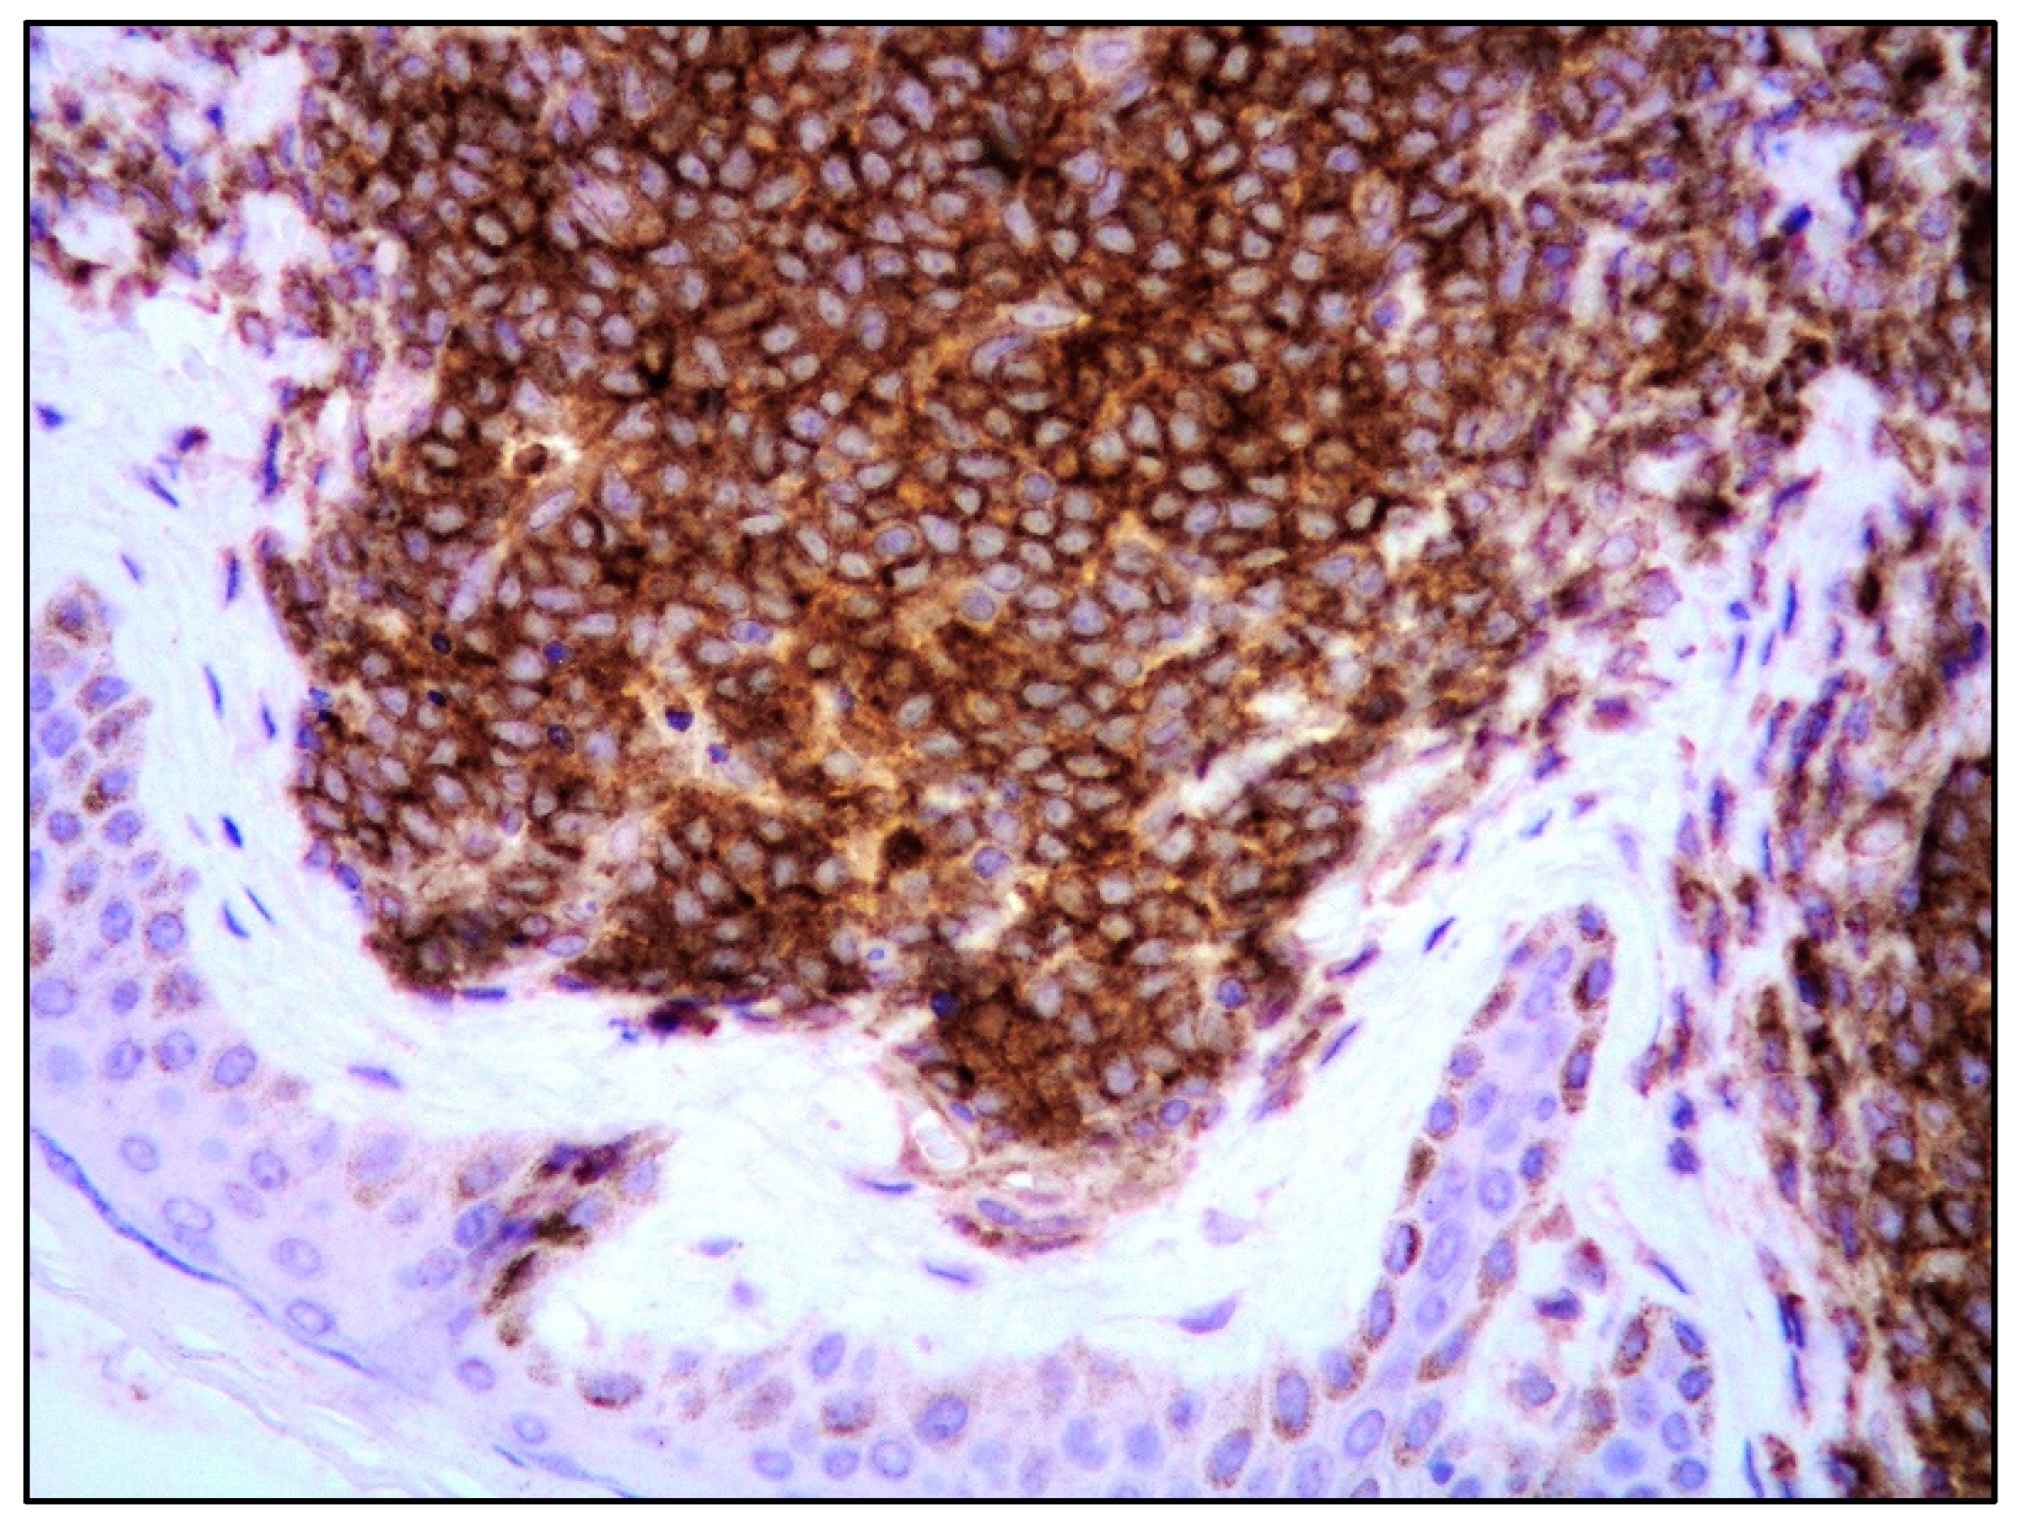

| Blastoid MCL | M:F = 3:1; late sixties | Solitary/multiple papules or nodules; often on extremities. Often previous history of MCL; skin lesions in recurrent and progressive disease | Diffuse dermal and subcutaneous tissue infiltrate; no epidermis and Grenz zone involvement. Monomorphic, medium-sized cells, round/oval nuclei, dispersed chromatin, inconspicuous nucleolus | Mature, naïve B-lymphocytes | CD20+, cyclin D1+, TdT−, CD3−, CD5+ (CD5 loss in 25-28% of blastoid MCL); aberrant expression of CD10, BCL6, CD23; TP53 overexpressed; high Ki67 | Poor. Intensive CT and immunotherapy plus ASCT; recently, anti CD19 CART cells, venetoclax, ibrutinib, acalabrutinib |